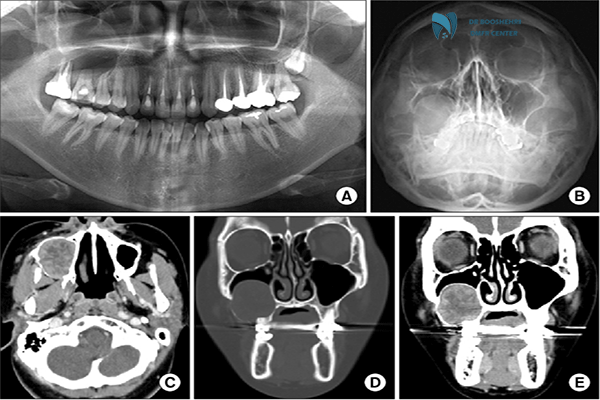

Other methods, such as Cone Beam Computed Tomography (CBCT), provide high-resolution images with low radiation doses, making them ideal for evaluating bony structures. Combining CBCT and MRI enables a more comprehensive diagnosis of TMJ disorders. Additionally, hybrid methods like PET-CT and PET-MRI, alongside artificial intelligence in image analysis, offer new perspectives for diagnosing and treating TMJ disorders.

Accurate diagnosis of TMJ disorders can be challenging without proper imaging techniques. TMJ imaging is one of the most advanced methods that assists physicians in diagnosing these conditions. These techniques include MRI for soft tissue visualization and CT scans for evaluating the hard bony structures.

Several imaging techniques are available for evaluating TMJ disorders, each with unique advantages and limitations. MRI stands out as one of the best options for visualizing soft tissues such as the joint disc. On the other hand, CT scans excel in depicting bony structures like joint surfaces and bone alterations.

Panoramic radiography is another commonly used method, offering a quick and general overview of the jaw and dental structures, though it lacks the precision of MRI and CT scans. For cases requiring more detailed information, three-dimensional imaging using advanced technologies can provide effective solutions.

Although the choice of imaging method depends on the specific condition and the physician’s initial diagnosis, combining multiple approaches can offer a comprehensive view of the TMJ’s status. This detailed evaluation plays a critical role in designing effective treatment plans.